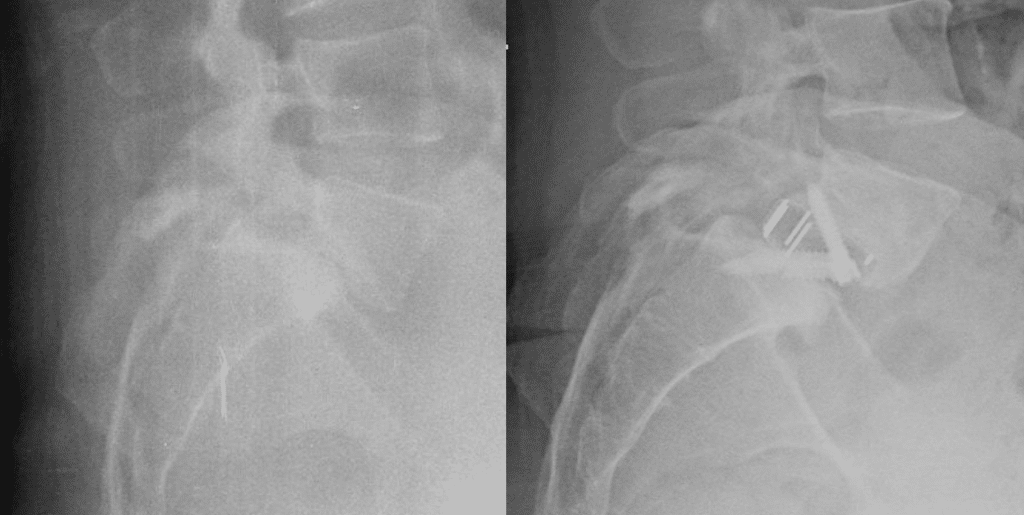

ALIF Standalone en la Espondilolistesis Ístmica: la Opción Disruptiva

En tuespalda.com, siempre buscamos las opciones más avanzadas y efectivas para el cuidado de tu columna. Hoy vamos a explorar un enfoque quirúrgico para la espondilolistesis ístmica, que está ganando terreno por sus beneficios tanto para el paciente como para el cirujano: la fusión vía anterior pura o ALIF standalone. Un Vistazo a la Espondilolistesis […]